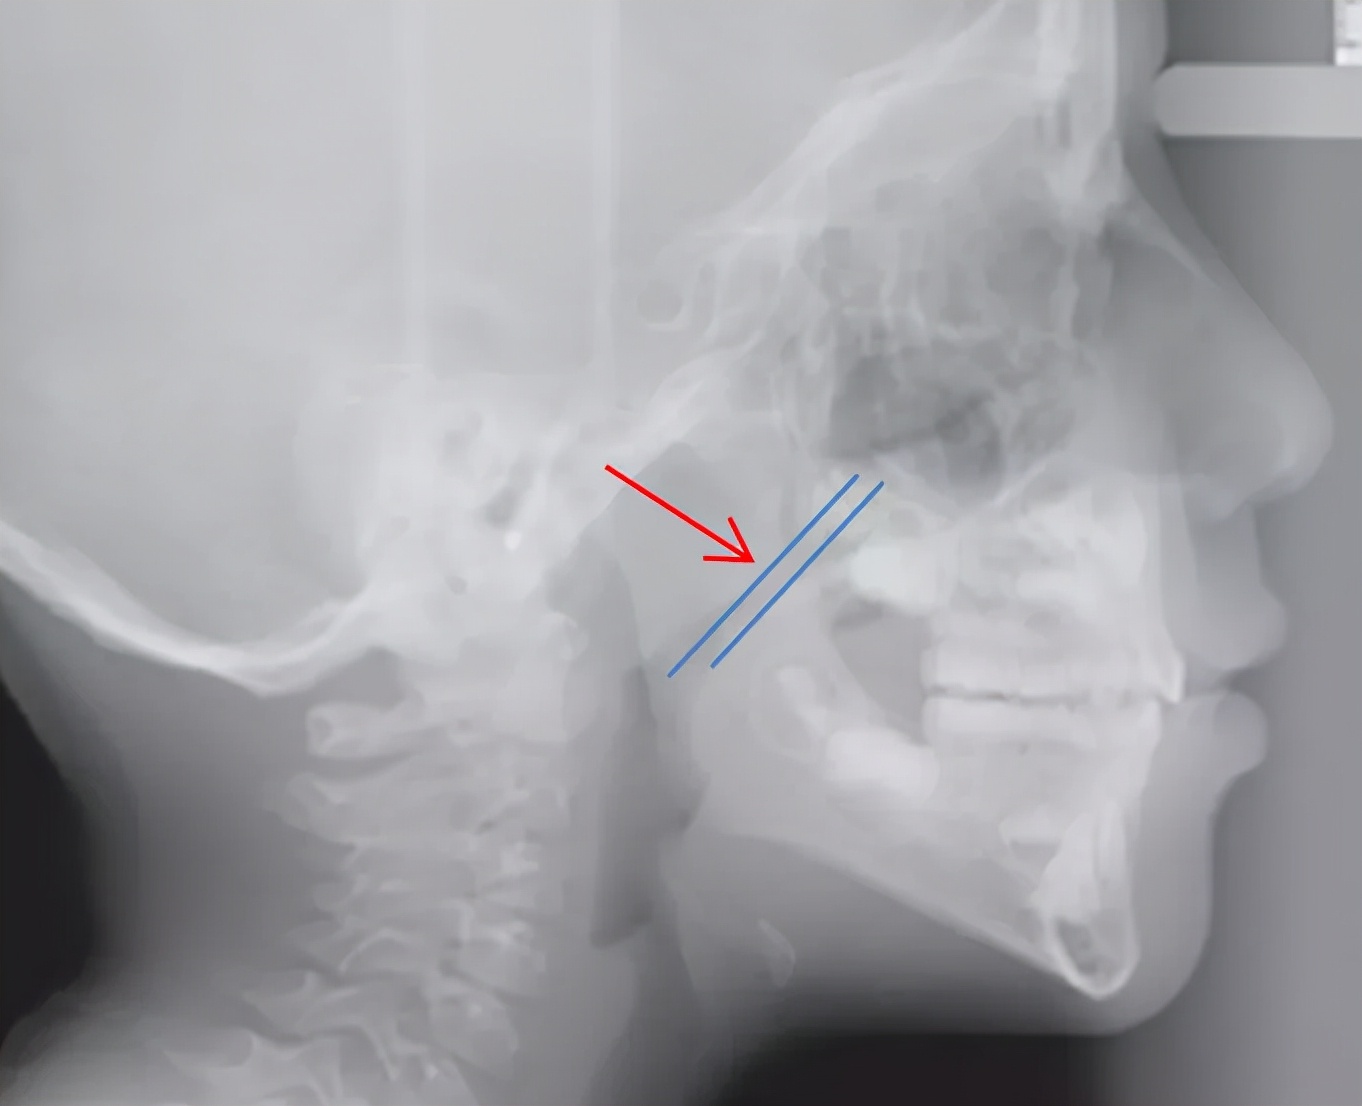

上面的片子是牙齿正畸时,最常拍摄的头颅侧位片。

从两张片子比较,能直观地看出:腺样体肥大的直接后果,就是气道明显变狭窄。(红色箭头表示腺样体,两蓝线之间表示气道宽度)。

头颅侧位片或CT影像检查,可见鼻咽气道阻塞变窄。(结合患者实际情况进一步选择)